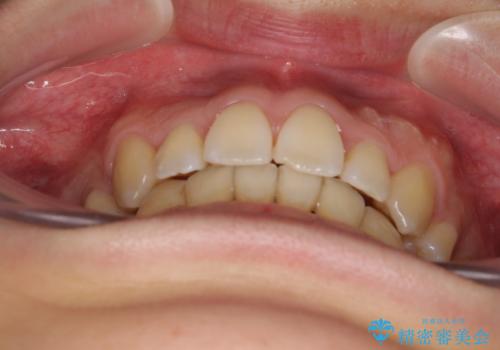

元の歯列が想像できないほど、きれいな歯列に整えることができました。

第二小臼歯抜歯の矯正治療は、治療期間が長引くことが多いですが、動きが非常に良く、予定の治療期間で終えることができました。